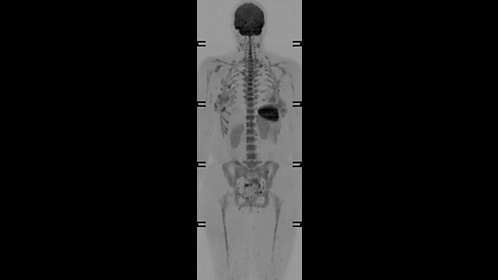

An integrated coil solution for whole body and peripheral vascular related imaging. It includes two dStream Torso coils. Combined with the dStream Posterior, HeadNeck and dStream Base it enables 200 cm coverage with a maximum of 108 channels. The flexible, lightweight easy-to-position dStream Torso coil is designed to conform both in right-left and foot-head directions to support virtually all patients. This allows large coverage and comfortable strap-free operation.